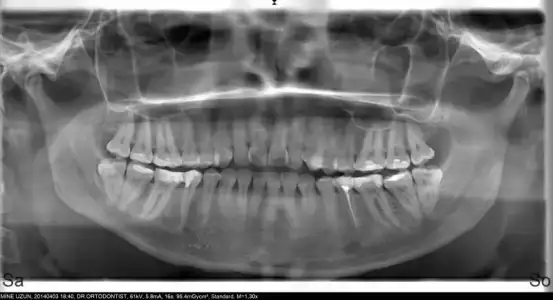

benımde 20 lık dişler alttakıler yarısı var yarısı yok .. ilk ortodontise gittiğimde cektı panoramık filmi .. 2 sene olucak nerdeyse ve çekılmesi lazım .. carsamba için cerrahtan alıcam randevu ınsallah.. diş kokunun nasıl oldugu önemli .. bak senın için röntgen resmini paylaşıorum .. sondan bir öncekı dişin kökü şemsiye ama allahtan o değil cekılcek olan :( kesilip eti yarıp cekıp dikış oluyormuş ama dr önemli bir faktör.. ve bencede cekılmelıkı ilerde sorun olmasın neticede kök diş ve agızda kullanılmıyor diş fırcasıda orayaı yeterlı temizleyemediği için çürüme yapıp yan dişlerede zarar verioo ..

Eklentiler

• PANORAMİK.webp

PANORAMİK.webp

16,1 KB · Görüntüleme: 97